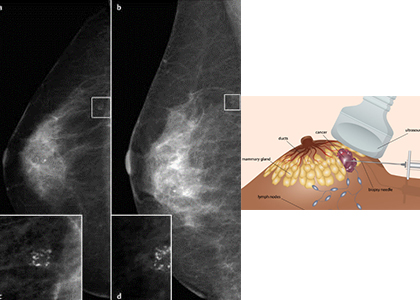

Stereotactic and Vacuum Biopsy

Accurate computer imagaing guidance allows precise localization of breast lesions which can be sampled by biopsy or removed with vacuum assisted biopsy. Vacuum assisted biopsy is an alternative to surgical biopsy and is performed under local anaesthetic.